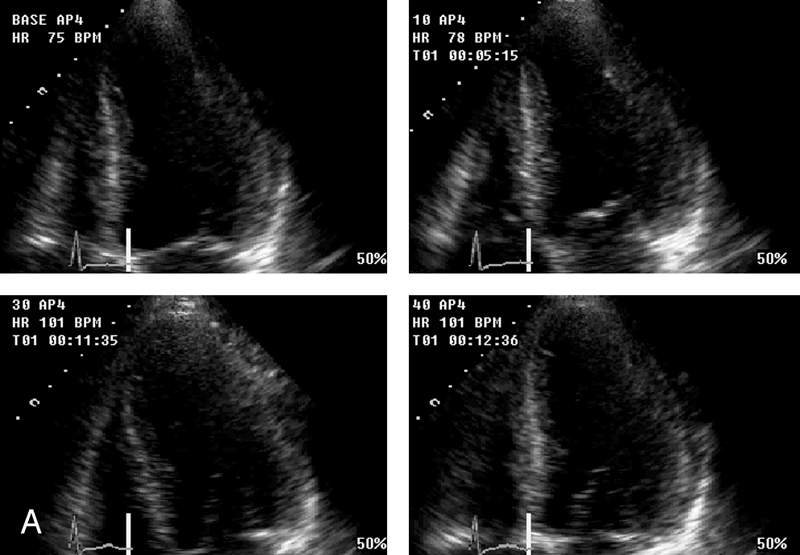

فحوصات تشخيصية لبعض امراض القلب والشرايين التاجية